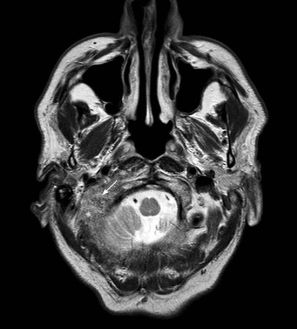

“Little is understood about what actually happens to our brains during orgasm – but a video taken an MRI scanner shows for the first time how many regions of the brain are affected. Scientists say that rather than a few, isolated areas of the brain being affected, the orgasm affects more than 80 brain regions. The scan was taken of Nan Wise, a 54-year-old sex therapist, who volunteered to sit in an MRI scanner while stimulating herself. Professor Barry Komisaruk, a psychologist at Rutgers University in New Jersey, hopes that the research will help women who find it difficult to orgasm.”